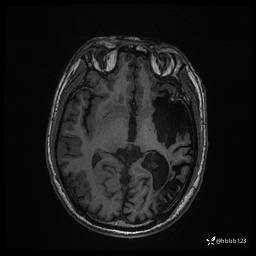

患者男,43岁。

简要病史:癫痫患者复诊,昨日发作5-6次,建议住院进一步治疗。

入院完善脑癫痫组合序列:

T2 Flair: